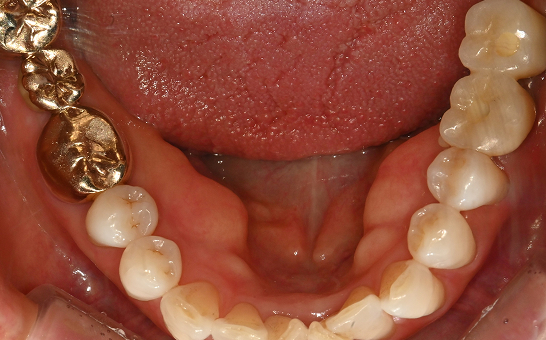

CASE 02 김** / 60대

전악임플란트

치료 시작 전 촬영 2024.01.24 | 치료 완료 후 촬영 2024.12.26

1 예후불량 치아 발치

2 발치 후 즉시 임플란트 식립 및 뼈이식

3 고정성 보철물로 수복 후 일상 회복